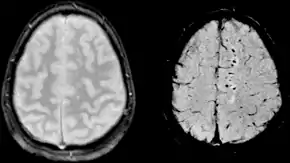

La lesión difusa se circunscribe básicamente a la lesión axonal difusa (LAD) y a algunos casos de tumefacción cerebral difusa (swelling). Una LAD es el corte de los axones en la sustancia blanca cerebral lo que causa la aparición déficits neurológicos no lateralizados como la encefalopatía. Las consecuencias de este tipo de lesión pueden tener un retraso de aparición de hasta 12 horas después del trauma. La LAD se produce por efecto de fuerzas inerciales que actúan sobre los axones durante unos 50 ms en sentido lineal o angular (por ejemplo, en colisiones frontales) lo que produce la desconexión y ruptura de los axones (axotomía primaria); no obstante la mayoría de los axones dañados (94%) son afectados por la axotomía diferida que consiste en un aumento a la permeabilidad de Ca++ en los nodos de Ranvier que causa la destrucción celular por excitotoxicidad. Ambas axotomías evolucionan desfavorablemente con cambios histopatológicos progresivos como son la formación precoz de bulbos de retracción axonal, acumulación de microglia y presencia de tractos de degeneración walleriana. La LAD puede ser identificada como hemorragias petequiales en la materia blanca (especialmente subcortical) en la TC y RM después de un TCE; sin embargo, los resultados pueden aparecer sutiles o ausentes en las imágenes. Los pacientes que padecen una LAD están subreactivos desde el momento en que se inflige el traumatismo porque la afectación axonal interrumpe las señales del sistema reticular activador ascendente y sus manifestaciones van desde una conmoción cerebral hasta la lesión axonal difusa grave.[8][5]

La evaluación radiológica inicial es la misma que para cualquier paciente con trauma: radiografía (Rx) de tórax, de pelvis y de columna cervical.[13] El estudio de neuroimagen de elección en el TCE es TAC de cabeza sin contraste. A pesar de que el 15% de los pacientes con TBI tendrá una lesión aguda detectada por TAC sin contraste, sólo el 1% de estas anomalías requieren intervención neuroquirúrgica.[49][50] Aunque la resonancia magnética (MRI) es un 30% más sensible que la TAC para la detección de anomalías traumáticas después de un TCE, no hay evidencia que identifica mejor a los pacientes que requieren intervención neuroquirúrgica.[51]